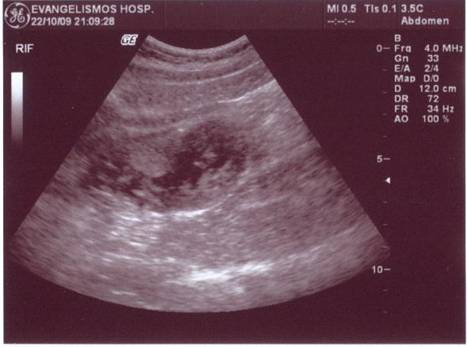

A 30-year old man presented with symptoms and signs of acute appendicitis. Abdominal imaging via ultrasound and computed tomography detected a mass in the right iliac fossa. Exploratory laparotomy revealed an appendiceal mass and gelatinous peritoneal fluid, while histopathology confirmed the diagnosis of pseudomyxoma peritonei arising from a mucocele of the appendix and attributed to an appendiceal cystadenocarcinoma. The clinical and imaging findings of this rare case are herein presented.